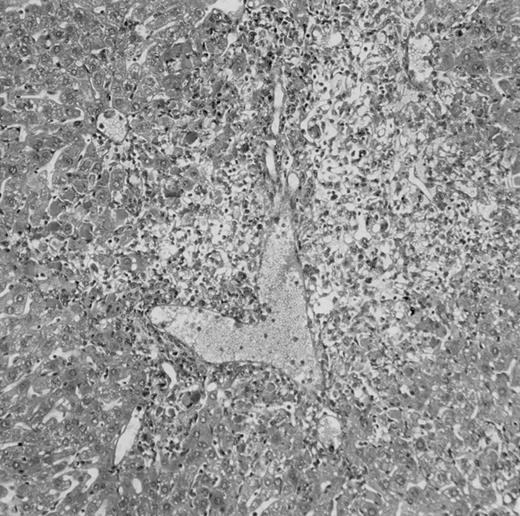

Histologic findings. Organs were collected at different times after BMT and tissue sections were stained with hematoxylin and eosin. Original magnifications for spleen (left) and liver (right) are ×40 and ×100, respectively. (A) B6 mice receiving FVB BM plus EpTK T cells. (B) Control group receiving BM only.

(C) B6 mice receiving FVB BM plus EpΔTK T cells and treated with GCV. (D) B6 mice receiving FVB BM plus EpΔTK T cells, treated with GCV, and developing a late onset GVHD (day 54).

FVB BM-grafted B6 mice: a model of lethal GVHD.We developed a model of GVHD resulting in 100% mortality soon after BMT using FVB mice, a strain not previously used as BM donors in experimental allogeneic BMT. We tested different combinations of recipient irradiation doses, as well as injected BM cell and CD3+ peripheral T-cell numbers. When 10-Gy–irradiated B6 mice were reconstituted with 107 FVB BM cells, we observed prolonged survival, whereas all ungrafted animals died before day 16 (Fig 2). In these conditions, more than 98% of splenocytes were of donor origin (Fig 3A). When 107 CD3+ peripheral T cells from mice of FVB genetic background were added to the FVB BMT, all animals died of GVHD between days 7 and 34 (Fig 2). Similar results were obtained using either PBS-treated mice receiving EpTK or EpΔTK peripheral T cells or GCV-treated mice receiving FVB nontransgenic peripheral T cells. Notably, this observation also indicates that both TK- and ΔTK-expressing T cells in the absence of GCV are fully competent to induce a lethal GVHD. Histopathologic examination of spleen and liver of these animals showed characteristic GVHD lesions such as (1) architecture disruption, necrosis, and congestion in the spleen; (2) hepatic periportal necrosis; (3) mononuclear portal infiltrates; and (4) endothelialitis of portal or centrolobular veinules (Fig 4A). By comparison, B6 mice receiving only FVB BM had a normal histology (Fig 4B).

On the other hand, 5 of 19 mice exhibited signs suggesting the occurrence of a delayed GVHD (Table 1). Clinically, these animals presented weight loss and/or skin lesions on ears, neck, limbs, or abdomen, but only after day 40. In the absence of any further GCV treatment, 2 mice died 14 and 29 days after the occurrence of these signs (Table 1A) with histological signs of severe GVHD (Fig 4D). These results suggest that, in these mice, the 7-day GCV treatment was sufficient to prevent early, but not delayed GVHD.